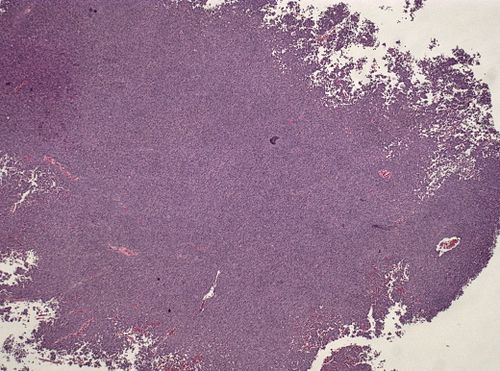

45 year old male with visual acuity disturbances

Site

Occipital lobe

Low magnification. H&E stain.

Metastatic malignant melanoma, BRAF V600E mutated